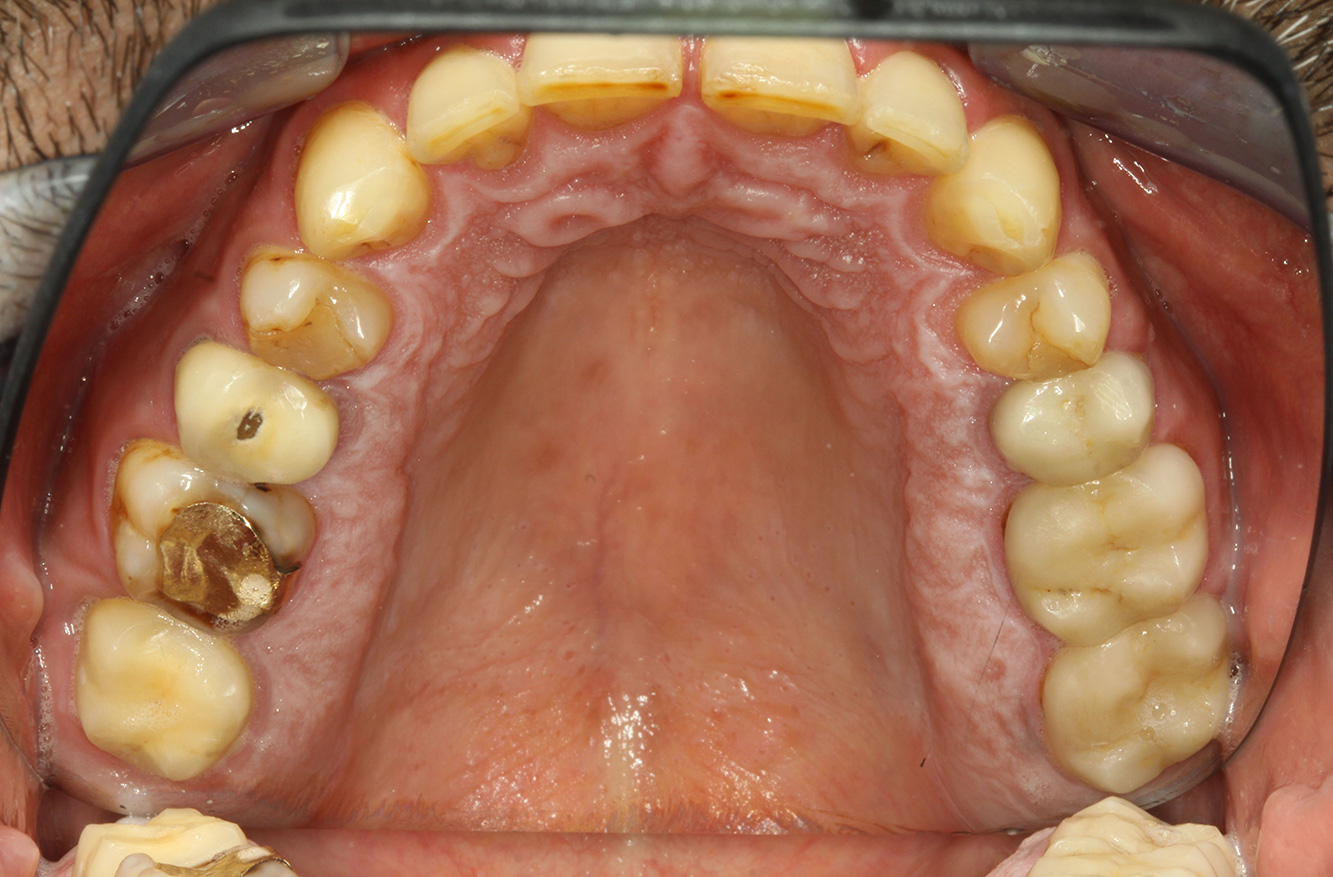

Il paziente ha 39 anni e in passato è stato sottoposto ad un intervento per la sostituzione della valvola aortica dovuta a insufficienza valvolare ed endocardite. Assume regolarmente l'ASS 100 come anticoagulante. Per quel che riguarda lo stile di vita, il regime alimentare seguito dal paziente è classificato come “dieta che favorisce la formazione della carie”, per via del consumo regolare di cibi ad alto contenuto di zuccheri e dei sei-sette pasti consumati al giorno. La salute orale del paziente indica un rischio moderato di carie, con lesioni attive. Il rischio di parodontite è basso, tuttavia il paziente è affetto da gengivite. Si formulano quindi i seguenti consigli per il trattamento di profilassi.

Bisogna dedicare tempo a sufficienza per il colloquio istruttivo/emozionale. Bisogna spiegare molto chiaramente al paziente l'impatto negativo delle sue abitudini alimentari sulla sua salute orale (9). Per quanto riguarda invece l'anamnesi di endocardite, si potrebbero analizzare anche i nessi tra batteri cariogeni e le malattie cardiovascolari (12). Questo argomento potrebbe motivare ulteriormente il paziente a cambiare il proprio regime alimentare. Durante il colloquio bisogna far comprendere al paziente quanto è importante seguire una corretta igiene orale a casa e motivarlo in tal senso.

Si consiglia una fluorizzazione per stimolare ulteriormente la prevenzione della carie, prevenire in particolar modo nuove formazioni intorno ai margini del restauro e per sigillare le superfici radicolari. Entrambi i provvedimenti possono ridurre la sensibilità dei denti alla temperatura.